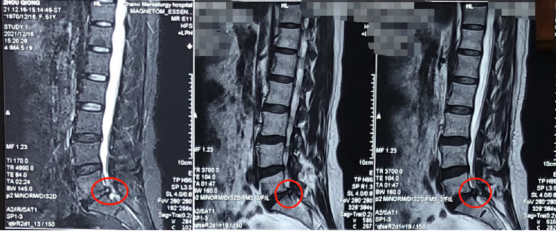

熊东主任接诊后,结合赵女士的查体及其他各项检查结果,确诊她为“腰椎间盘突出症(腰5骶1)”。赵女士在腰5骶1处已经出现比较严重的突出且已压迫到神经,而且症状严重影响生活,建议进行椎间孔镜手术微创治疗。

术前影像学资料